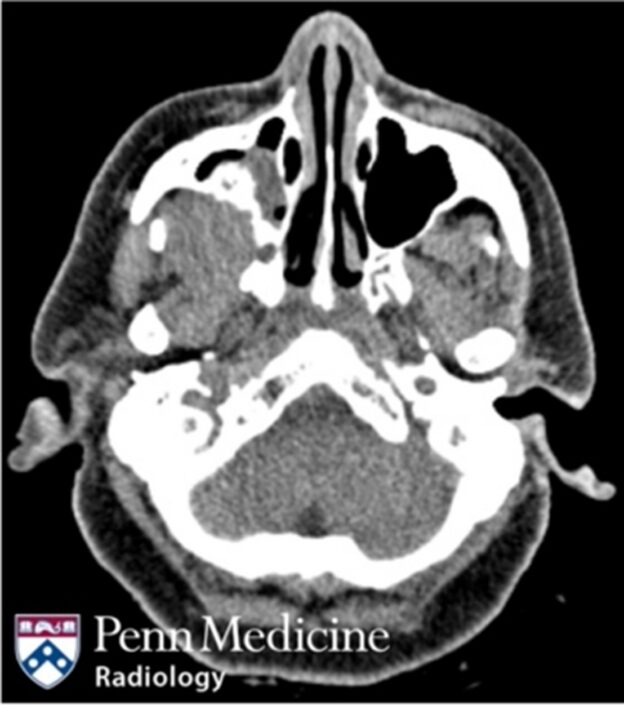

52-year-old woman with vertigo and sinus congestion

A 52-year-old female presented to the emergency department for vertigo and sinus congestion.